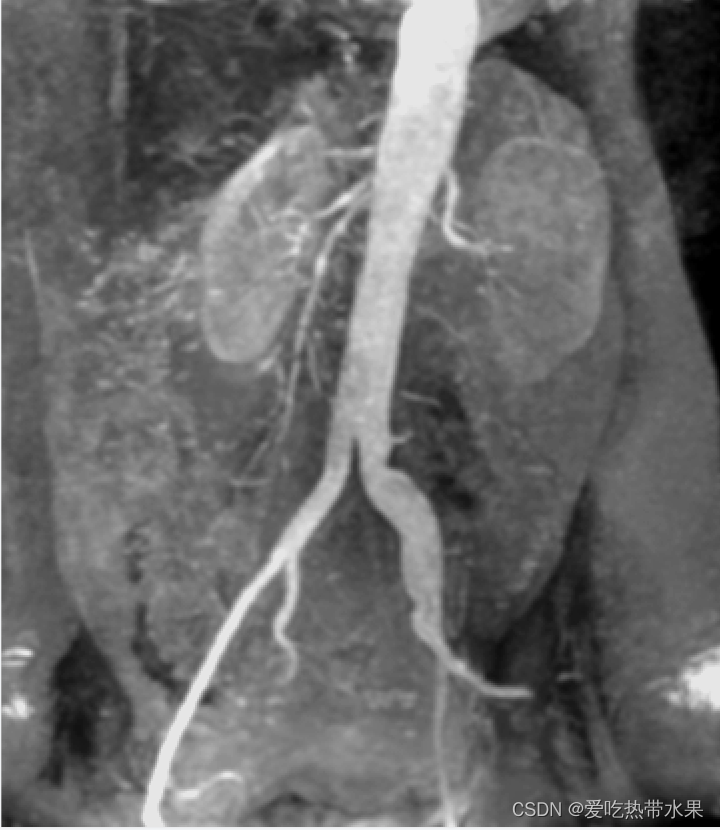

cv::Mat readImg = cv::imread("D:\\book\\image\\DIP3E_Original_Images_CH03\\Fig0312(a)(kidney).tif");

cv::cvtColor(readImg, image1_gray, COLOR_BGR2GRAY); //灰度化

for(int i = 0; i < image1_gray.rows; i++)

{for(int j = 0; j < image1_gray.cols; j++){//小于155大于245的灰度值改为0if(image1_gray.at<uchar>(i,j) < 155 | image1_gray.at<uchar>(i,j) > 245){image1_gray.at<uchar>(i,j) = 0;}else{image1_gray.at<uchar>(i,j) = 255;}}

}

cv::imshow("image",image1_gray);

cv::waitKey(0);

方法二:让感兴趣的范围变亮或变暗,其余部分不变

#include

cv::Mat image1_gray; //灰度图

{for(int j = 0; j < image1_gray.cols; j++){//感兴趣的部分灰度值改为255其余不变if(image1_gray.at<uchar>(i,j) >= 155 && image1_gray.at<uchar>(i,j) <= 245){image1_gray.at<uchar>(i,j) = 255;}}

001.jpg | 002.jpg | 003.jpg |